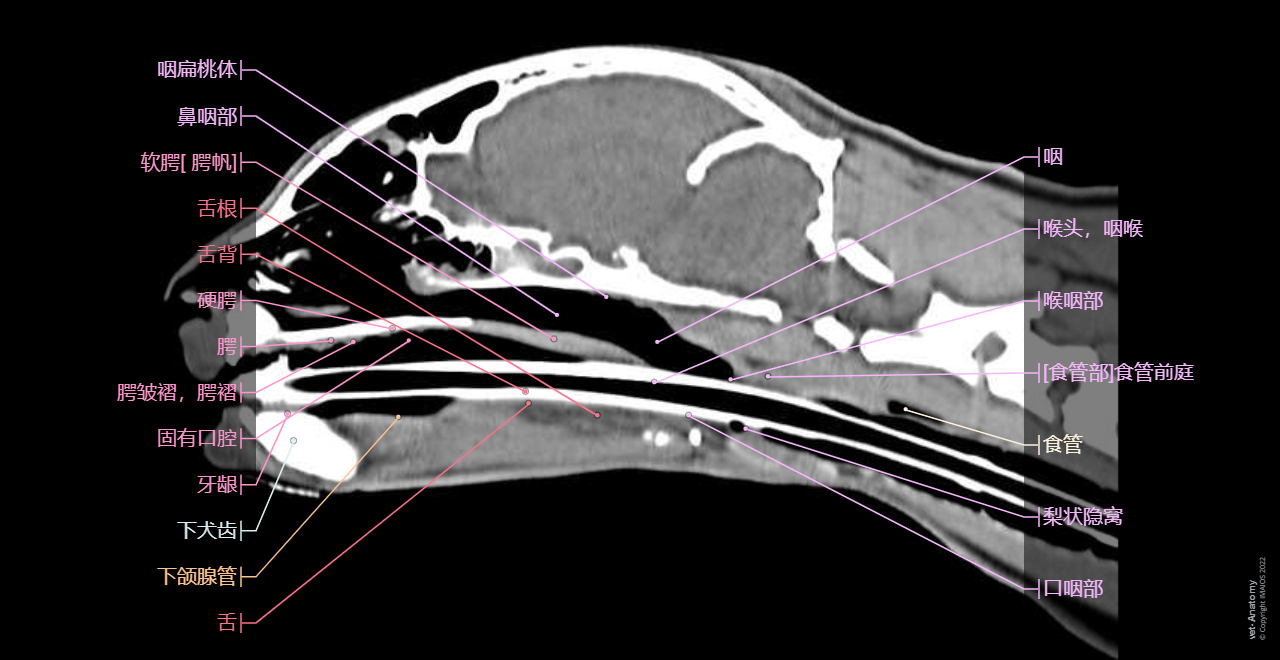

正常猫的头颈部CT解剖

- Antoine MICHEAU, MD , Denis HOA, MD , Susanne AEB Boroffka, PhD - dipl. ECVDI

- 发布日期: 2019年10月11日 | 最新更新 2025年3月18日